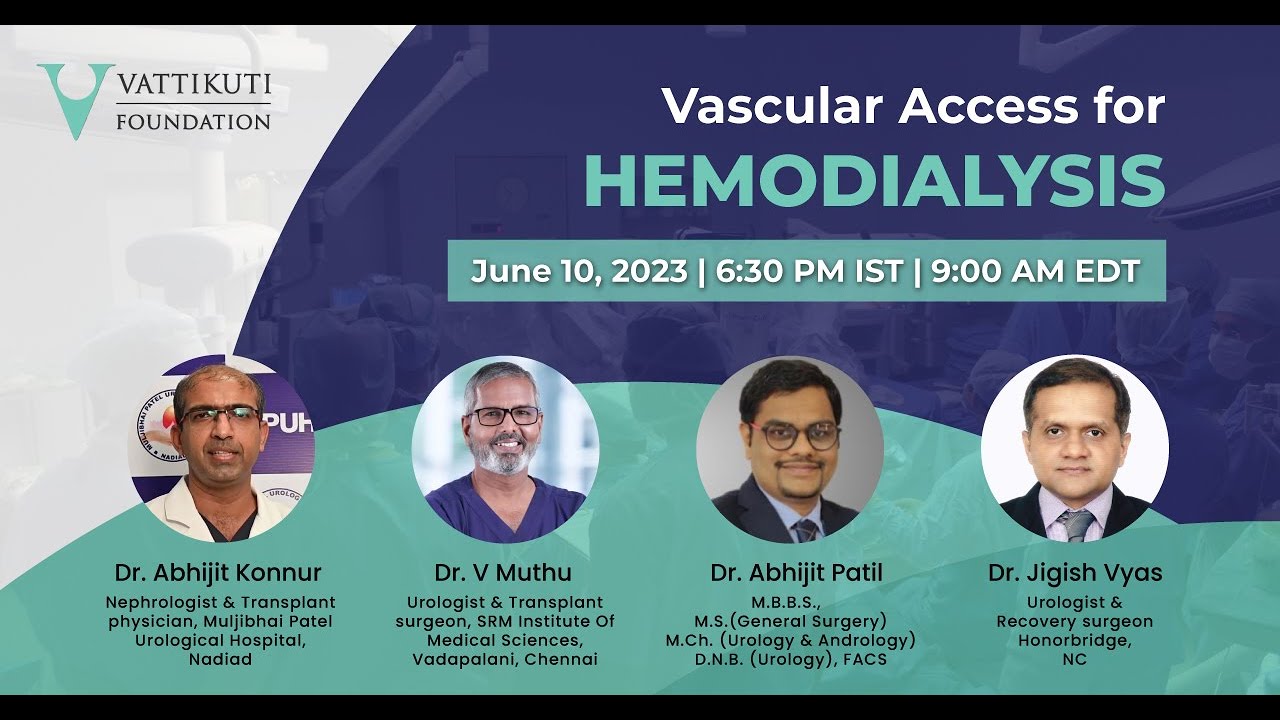

Hemodialysis and Hemodialysis Catheters – Dr. Abhijit Konnur

Masterclass, Robotics, Surgeon, Urology ';

VF Masterclass: Vascular Access for Hemodialalysis June 6, 2023

Masterclass, Robotics, Surgeon, Urology ';